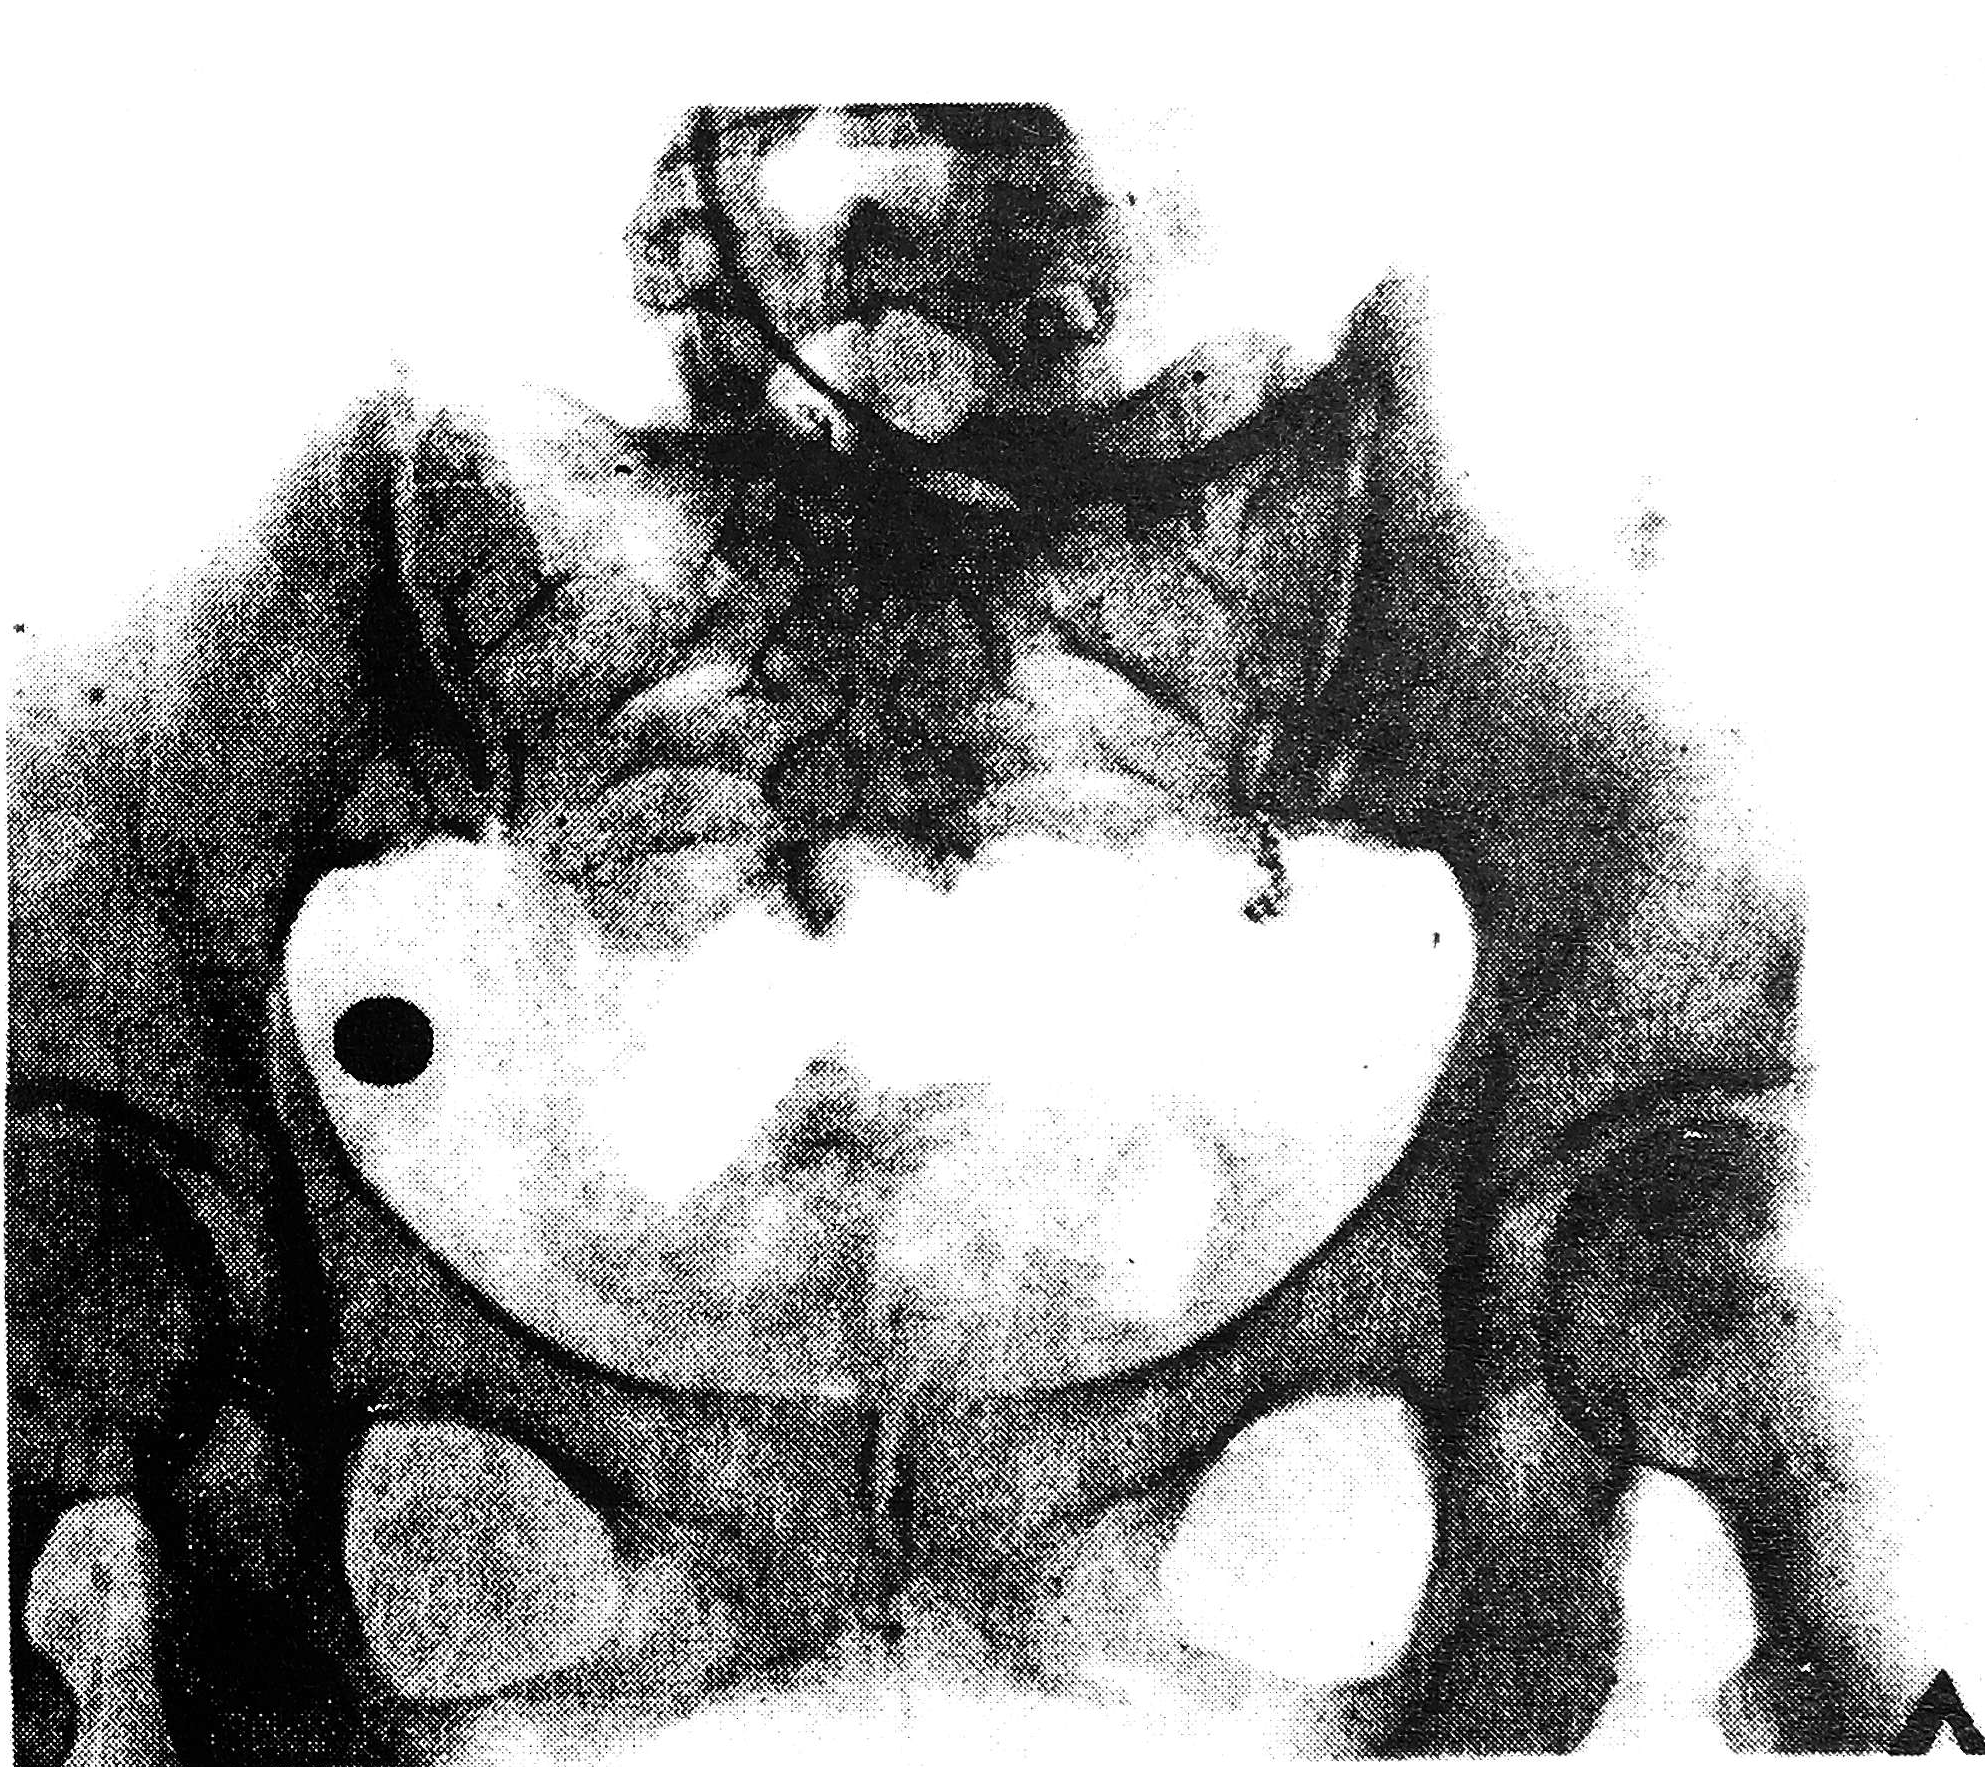

При рентгенологическом исследовании малого таза в правой половине его определяется инородное тело металлической плотности (пуля) (рис. 1).

Рис. 1. Рентгенограмма. Справа отчетливо видно инородное металлическое тело - пуля.